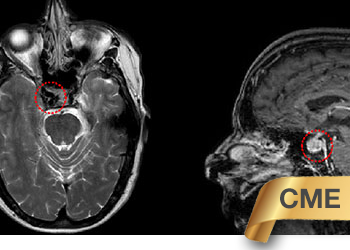

Brain:

Pineal Region Meningioma

Author: Michael Brisman M.D., F.A.C.S., Read More!